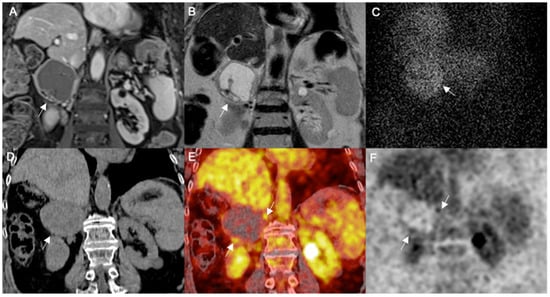

3.2.2. Atypical Pheos